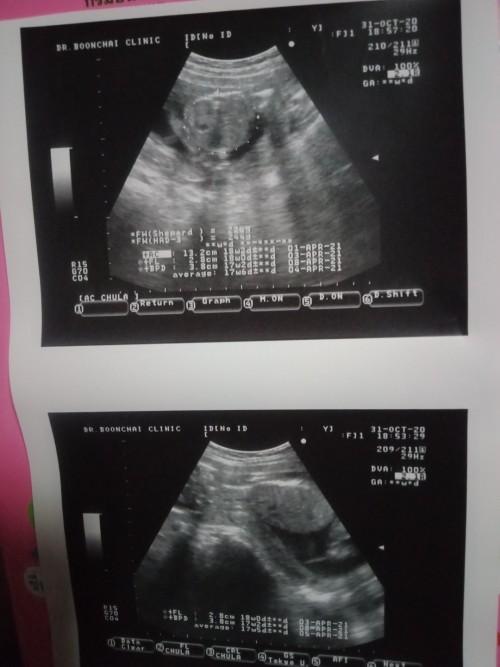

น้องนอนคว่ำแบบนี้ผิดปกติไหมค่ะ ไม่เคยเห็น เคยซาวด์มามีแต่นอนหงาย😟#ขอบคุณสำหรับคำตอบค่ะ กังวลใจผู้ใหญ่ที่บ้านถามมา ซาวด์หมอก็ไม่ไก็ว่าอะไร ได้ยินแล้วใจไม่ดีเลยค่ะ😟

ปกติคะแม่ น้องลอยอยู่ในน้ำคล่ำดิ้นเปลี่ยนท่าไปได้เรื่อยๆคะ บ้านนี้ก็ซาวด์เจอนอนคว่ำแบบนี้ตอน19วีคคะ